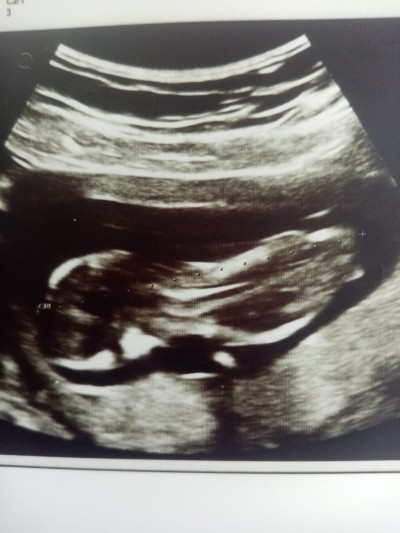

Normalde 12+3 doktorumda 13+1 dedi cinsiyet nedir sizce bide bebek ters mi duruyor anlamadım